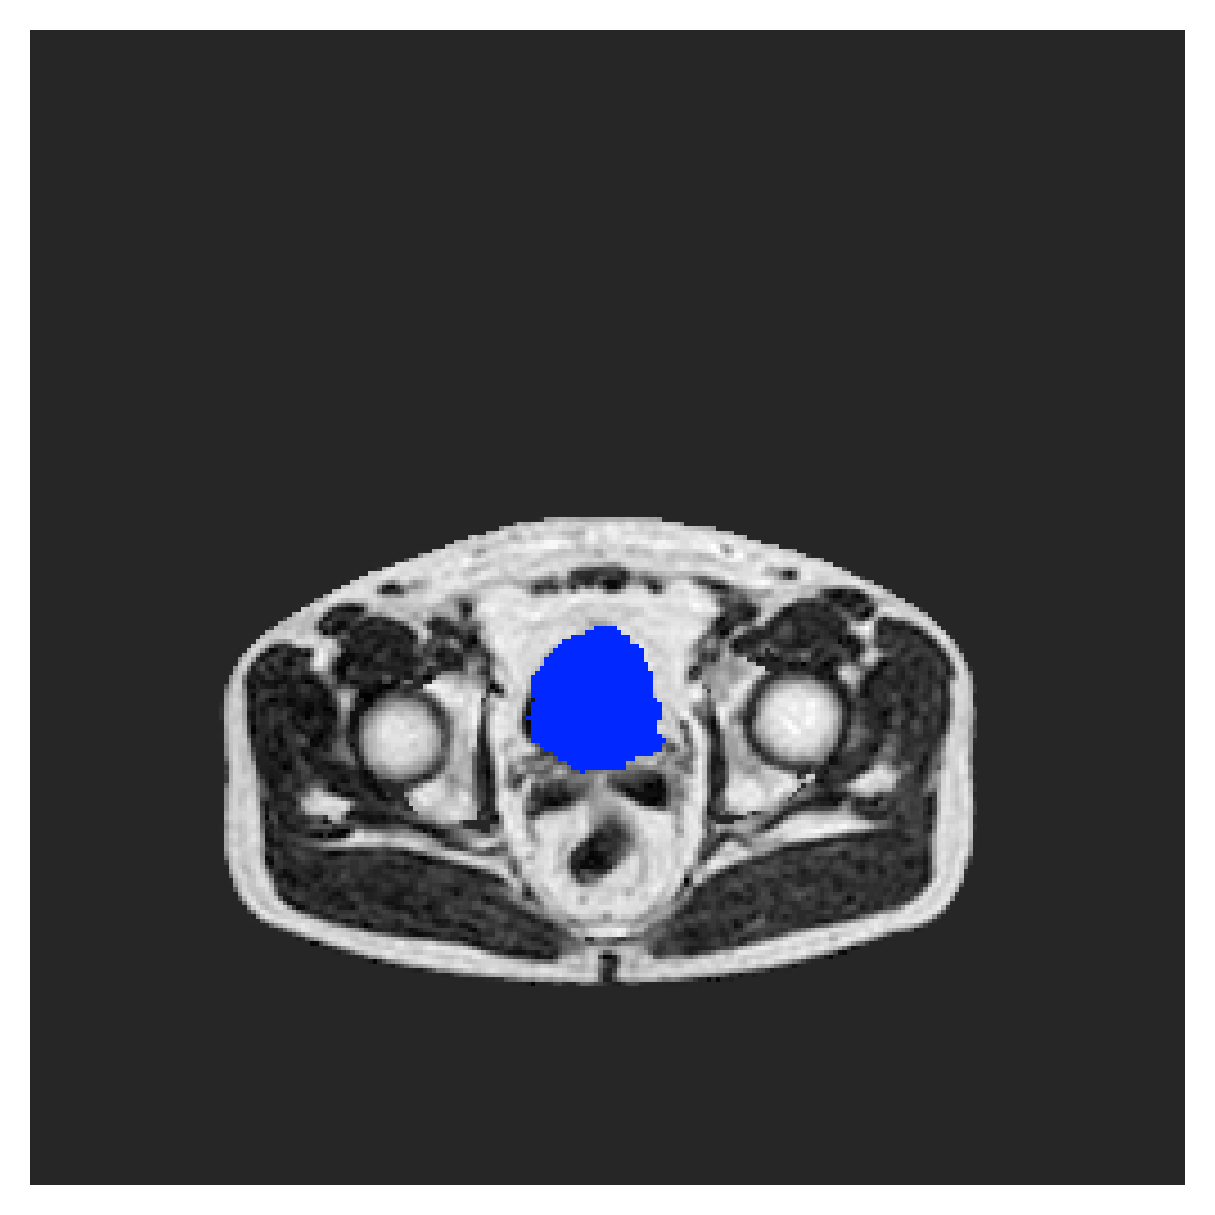

We normalize the volumes and resize the slices to pixels. As the official dataset comes with full annotations, we create a synthetic point ground truth. This is done by first randomly choosing the centers of the point annotations within the class masks, followed by filling an ellipse with axes lengths of and (in pixels) around each center. The intersections of these elliptic discs with the underlying full annotations are then used as our point ground truth. See Figure 2 for an example of the created weak annotation mask. The point annotations are created for every slice, one for each foreground object present in the slice.

The images contain two channels, one for water and one for fat content. For training, we normalize the volumes (per channel) and use 2D slices in the coronal plane, sized . The weak annotations are created synthetically, following the same procedure as described for the ACDC dataset.

In Figure 6 we provide qualitative results on a number of randomly chosen test set slices. Upon visual inspection, we can observe that training with the intensity-aware distances (particularly with and ) follows the image gradients better and is better at recovering the underlying shape than the Euclidean version. The CRF-loss seems to recover the shape of the myocardium and left ventricle to some extent, but fails entirely on the right ventricle.

5.2.1 Qualitative comparison

In Figure 11 and 12 we show the same random slices in cases of calculating the boundary loss on 2D- and 3D-based distances, respectively. Comparing the two figures again indicates that the intensity-aware distances offer most improvement when calculated in 3D over 2D. The exception here is the MBD, which seems to even slightly degrade for most classes.